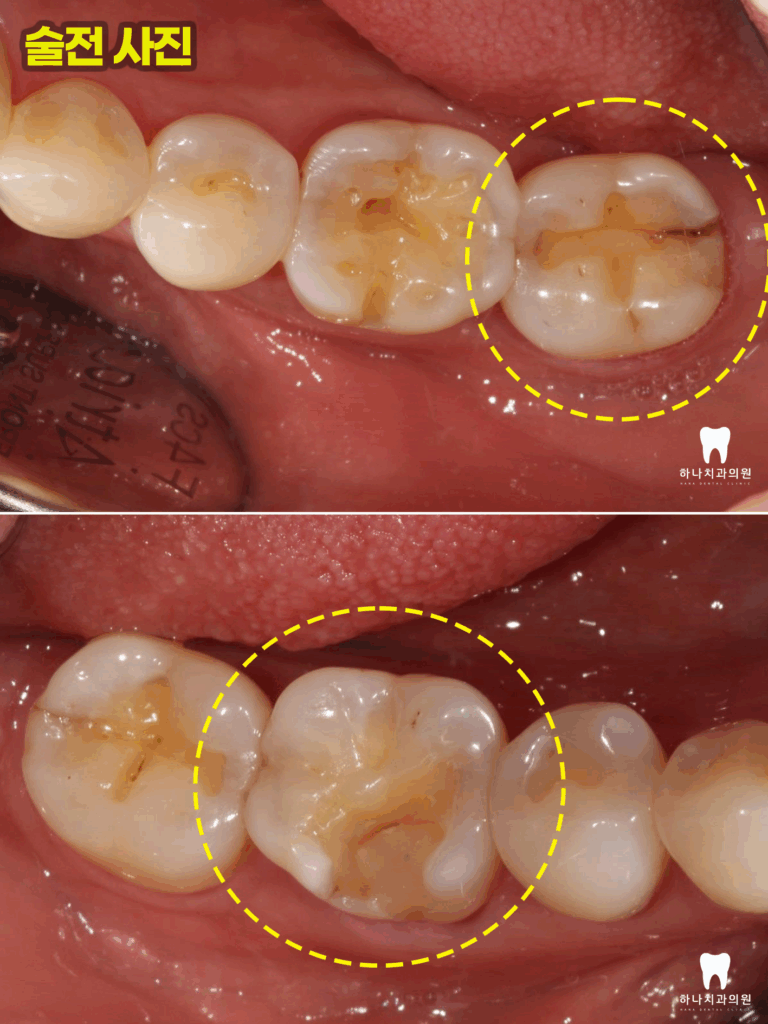

오른쪽 아래 어금니의 경우

사진에서 명확하게 보이지는 않지만

뿌리 끝까지 진행된 치아의 수직 파절로

탐침자로 만져보았을 때 완전히 반으로

갈라져 있는 상태였습니다.

왼쪽 아래 어금니는 다행히도

치아머리 부분만의 파절을 관찰하여

오른쪽은 발치 후 임플란트 수복,

왼쪽은 신경치료 후 크라운 수복을

계획하였습니다.